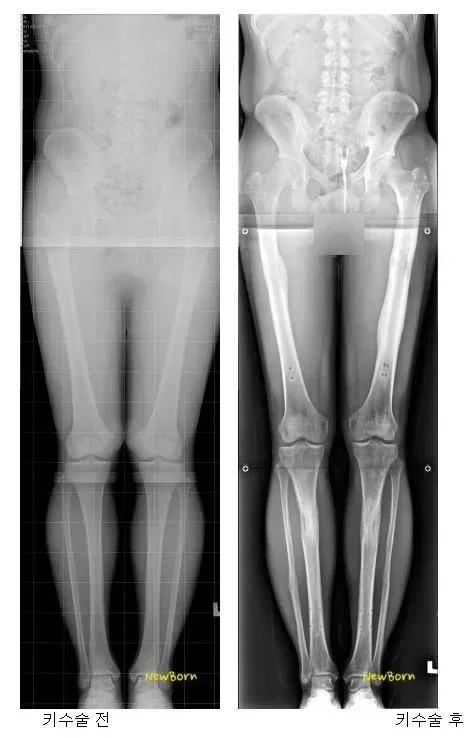

(약혐) 키 13cm 연장한 사람

인생걸고 받을 만큼 키 스트레스가 엄청 났을듯

고생한 만큼 좋은 일만 가득하길